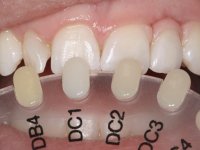

An impression was made on the implant with open tray technique using soft and regular consistency putty. At the laboratory, after confection of the work model, a diagnostic waxing was performed, which sought to find an aesthetic compromise solution. In this sense, a temporary workpiece screwed onto the implant was used to simulate the difficulties we would have with screwing the definitive work. This study abutment consisted of wax to reproduce soft and hard tissues, seeking to anticipate the use of ceramics of gingival and coronary shade. Also, part of the interproximal papillae corresponding to the distal portion of the 2.1 tooth and the mesial tooth of the tooth 2.3 were also waxed, anticipating the use of composite resin “chips” with gingival tonality. Finally, a veneer was waxed to correct the microdontia of the tooth 1.2. In this waxing, the vestibular emergence of the orifice for access to the screw of the implant abutment was evident. Once this therapeutic option was accepted, the implant abutment in polymerized composite resin was prepared at the lab, as well as the papillary "chips", also in composite resin of gingival tonality. Tested in the mouth, the abutment was screwed and the "chips" bonded. The access hole of the screw was filled with composite resin. In subsequent consultation, a gingivectomy was performed on the cervical contour of teeth 1.3, 1.2 and 1.1 with the aim of correcting the asymmetry between the first and second quadrant. After the soft tissues were cicatrized, a dental bleaching was performed according to the patient’s aesthetic requirements. Final impression on the implant was made using the silicone open tray technique, taking care to individualize the transfer piece by copying the emergence profile of the patient’s provisional abutment. At the laboratory, the impression yielded a definitive working model, on which the abutment was waxed on a plastic insert. This process was carried out with the orientation of a wall of silicone based on diagnostic waxing. The wax made on the plastic part was placed in a special holder that allowed its scanning in a laboratory scanner. This scan by CAD process informed the design of an abutment in Zr. later materialized by a CAM process. The Zr. abutment was tested in the mouth, validating its clinical and imaging establishment. During this consultation, the choice of color was made by the ceramist, of both the coronary ceramics and the ceramic of gingival tonality to be used. Individualized color scales were used. At the laboratory, the coronary and gingival ceramics were placed on the implant abutment and later, on a working model with refractory gypsum, a veneer of feldspathic ceramic was made. This veneer was built on a surface specially designed for this purpose in the abutment. This surface tried to reproduce a dental preparation performed for the same effect. In the mouth the abutment was screwed with a torque of 35N, the access hole to the screw was filled with Teflon and later filled with composite resin. The veneer was bonded onto the implant abutment using the conventional bonding technique, with relative insulation. For economic reasons, the patient did not proceed to perform the veneer on tooth 1.2. Although a limited aesthetic compromise was expected from the outset, a result was achieved which satisfied the patient.